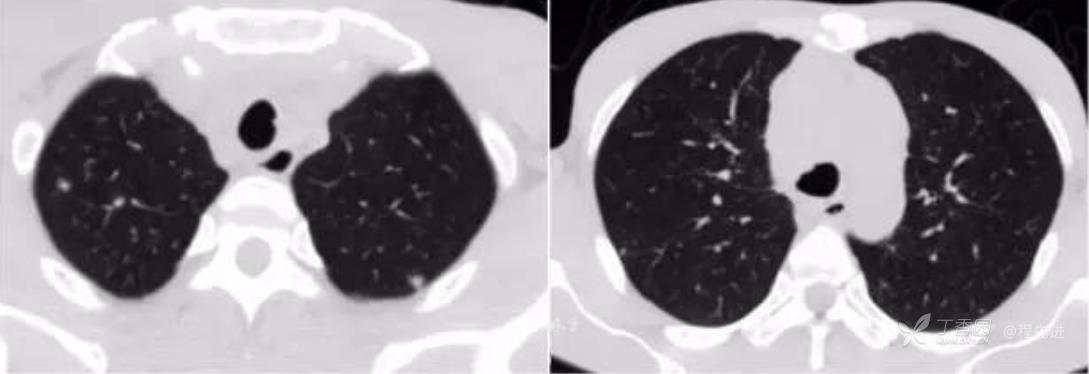

CT平扫肺窗